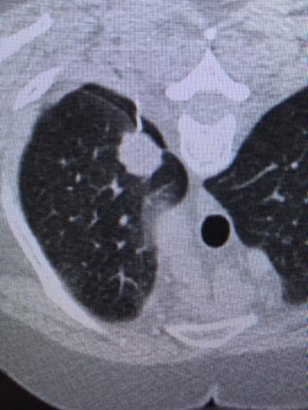

Scanner thoracique

Le scanner (ou tomodensitomètrie) est un appareil de radiologie qui utilise des rayons X et qui permet d'explorer différents organes du corps humain. Son principe consiste à produire des images en coupes du corps humain à des fins diagnostiques. Les rayons X qui traversent votre corps sont plus ou moins arrêtés en fonction de la densité des tissus. Les données obtenues sont traitées par informatique pour donner des images.Ce sont ces images qui sont analysées par le radiologue.